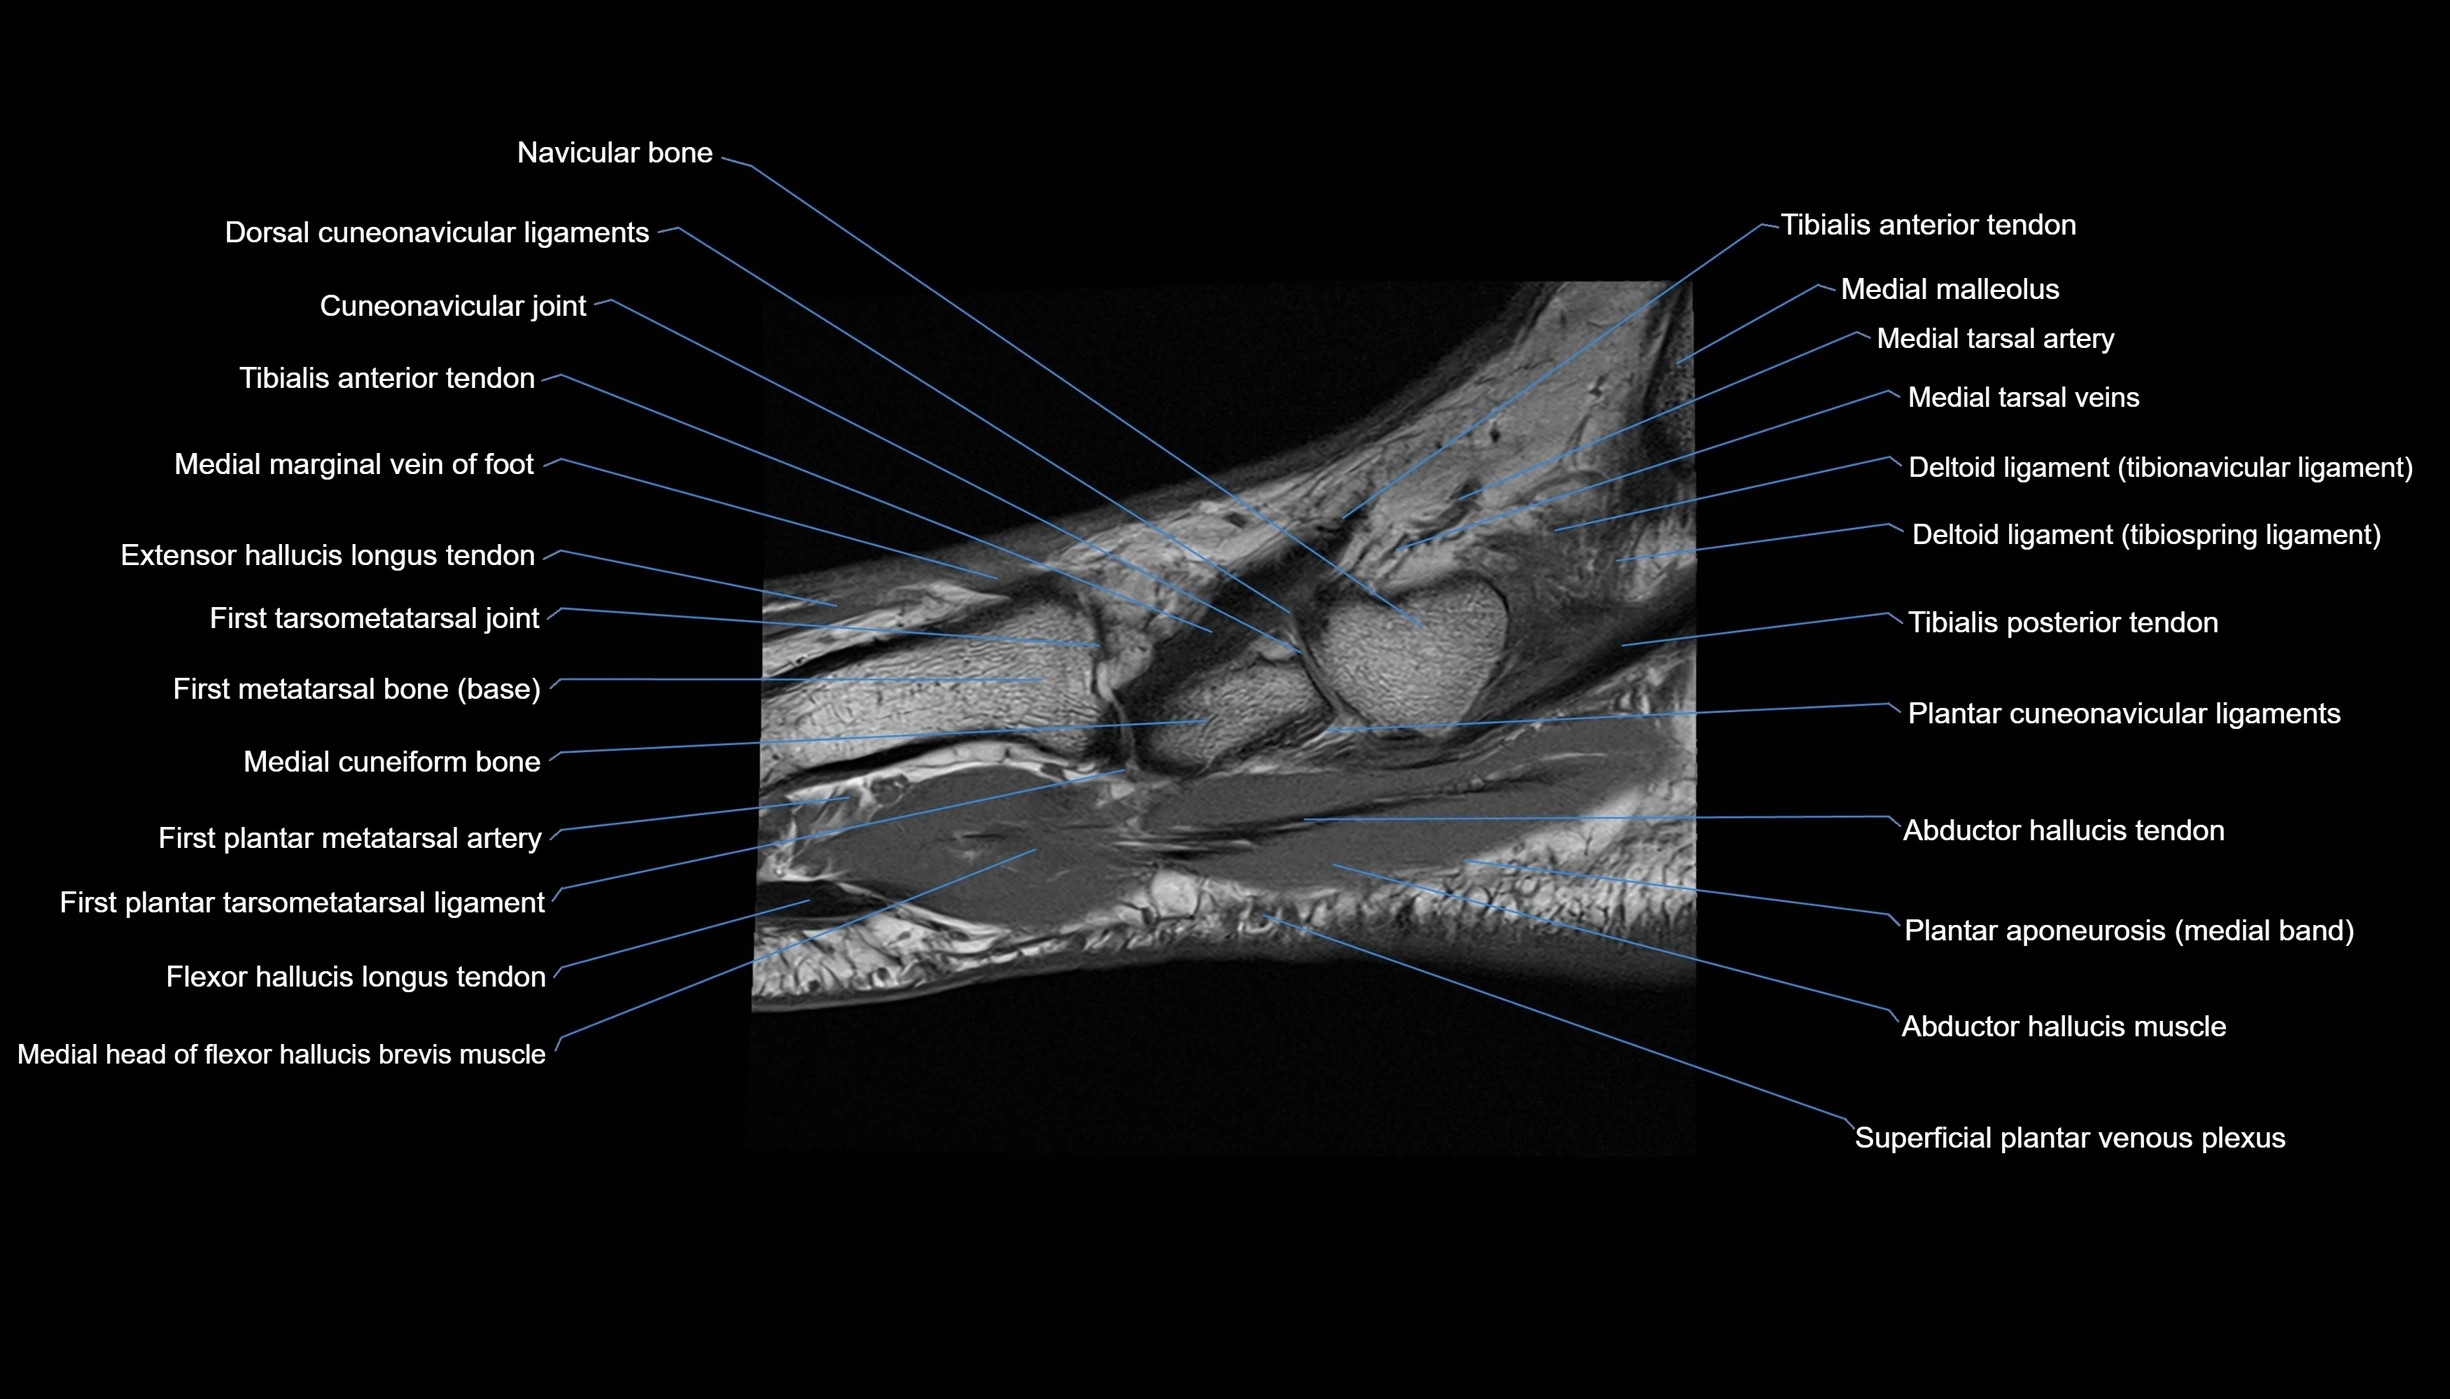

MRI image